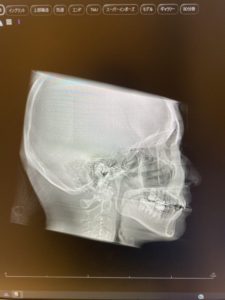

・精密検査

・定期チェック

・適切な力の調整

を行っていれば、リスクを最小限に抑えられます😱